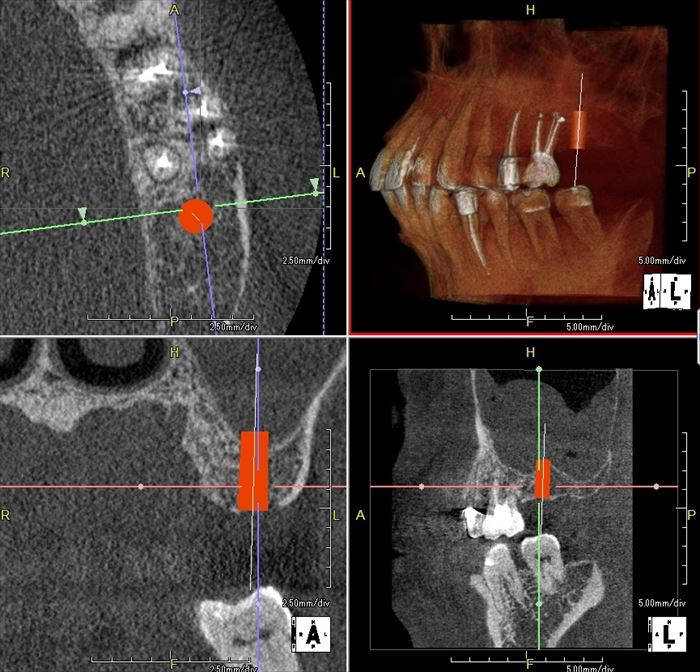

H・Tさんの左上第二大臼歯部分にインプラント埋入オペを計画します。

歯槽頂が かまぼこ型であることから可能であれば歯肉を切開しないフラップレス埋入オペを行います。

花粉症の時期であり、CT撮影時の上顎洞には粘液の貯留もしくは粘膜の肥厚があります。

上顎大臼歯部分にインプラントを埋入する場合、上顎洞底を挙上するソケットリフトを多くのケースで行います。

ソケットリフトを行うことで上顎骨の厚みよりも長いインプラントを埋入することが出来ます。

テーパーのついたインプラントを用いると、インプラントの先端が上顎洞底の硬い皮質骨に食い込むことにより

より強い初期固定を得ることが出来る場合があります。

H・Tさんのケースではソケットリフト時に上顎洞底の粘膜(シュナイダー膜)を破らないようにすることが重要です。